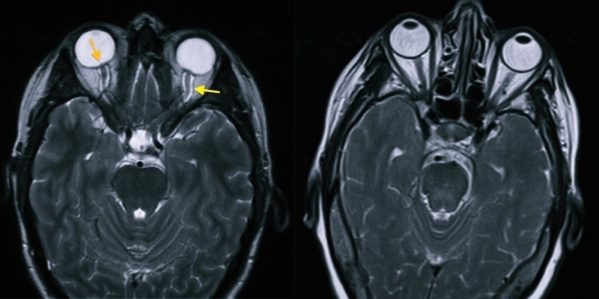

Если при синдроме внутричерепной гипертензии симптомы не будут купированы с помощью медикаментов и хирургического вмешательства, а продолжат развиваться, то произойдет резкое ухудшение зрения. Поэтому при подозрении на ВЧГ пациента обязательно отправляют пройти окулиста, который проведет осмотр глазного дна. В процессе проведения этой процедуры могут быть выявлены застойные диски зрительных нервов. При серьезном развитии внутричерепной гипертензии, застойные диски будут сменены на их вторичную атрофию. Из-за этого происходит нарушение остроты зрения, которую будет невозможно откорректировать с помощью линз. Атрофия зачастую заканчивается тем, что человек становится полностью слепым.

- Сначала пациента отправляют к офтальмологу, который должен осмотреть глазное дно.

- Затем больному необходимо пройти рентгенографию и получить снимок черепа. Более предпочтительным решением в этом случае является проведение КТ или МРТ, потому что с помощью этих исследований можно будет получить данные не только о костных мозговых структурах, но и о мозговой ткани, сосудах. Эти процедуры необходимы для определения первопричины повышения давления внутри черепа.